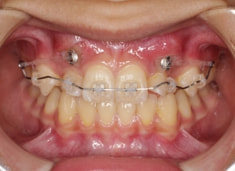

治療前

治療開始時